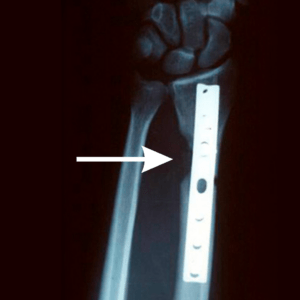

Follow up X-rays 27 years later

Before X-Rays were taken in 1996 and demonstrate bone loss from saw injury one week post op bone grafting.